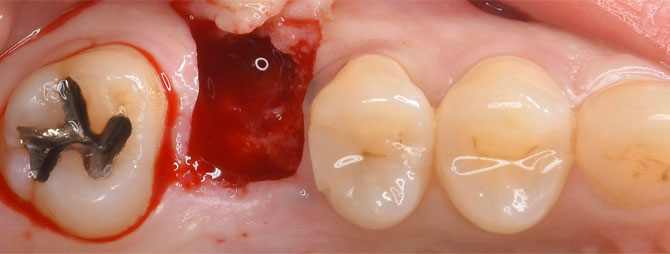

抜歯して約6週間後の口腔内写真。

痛みと腫れを最小限にするために、小さいエリアのみを切って開きます。

小さい穴を開けて、そこからドリルを逆回転で回して、柔らかい骨を圧縮して広げていきます。

上顎洞底粘膜を意図的に破くことで、インプラントが収まるスペースを作ります。

更にドリルを逆回転で回して、ご自分の骨を上顎洞側に押し込んでいきます。

骨ができるスペースを確保するために、コラーゲン製剤を置いてきます。

直径6ミリ長さ7ミリのワイドショートインプラントを、定位置に埋め込んでいきます。